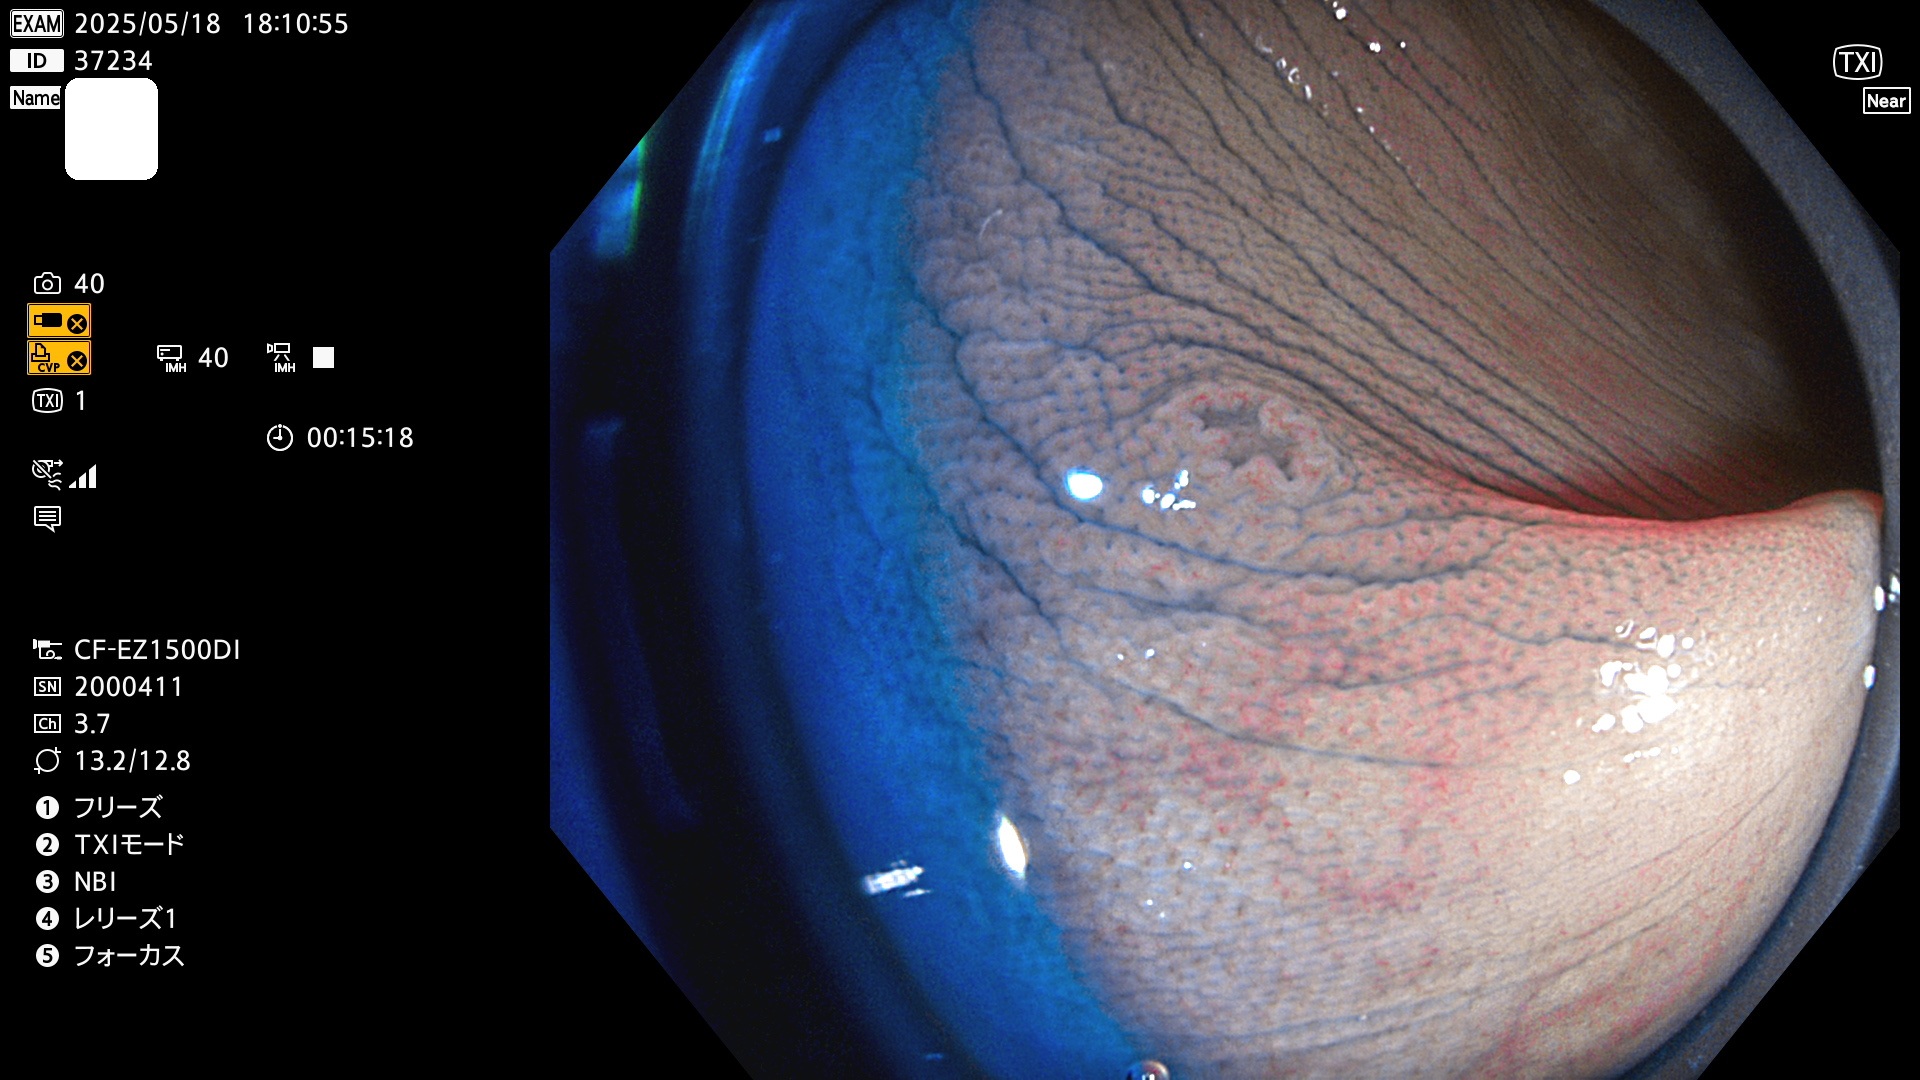

今週のUb、Uc型腺腫

完全に平坦な物をUb、陥凹している物をUcと呼びます。Ubは認識が困難で、Ucはびらん(炎症)と紛らわしいために見落とされやすく、「内視鏡後・大腸癌」の原因になります。

抽出の対象期間 2025年5月15日〜5月18日の4日間(48件の検査)6個 (6/48=13%)